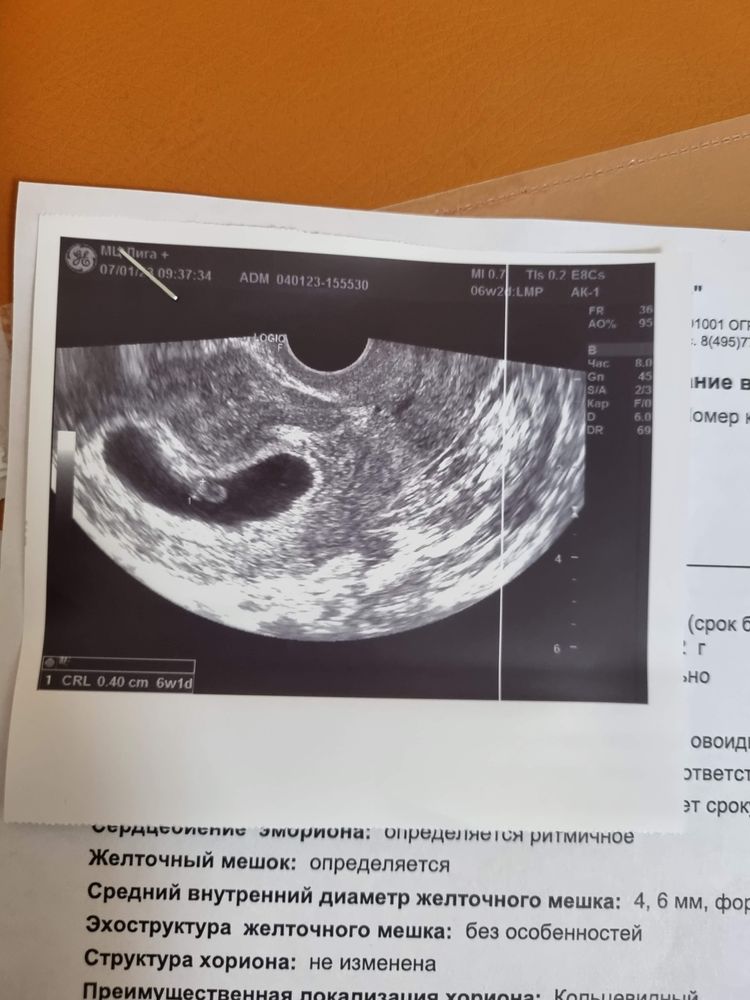

У меня 2года назад по числам, как у Вас: месячные 27.09, 10.11 не было даже ЖМ, 13.11 был уже эмбрион крохотный Изображение